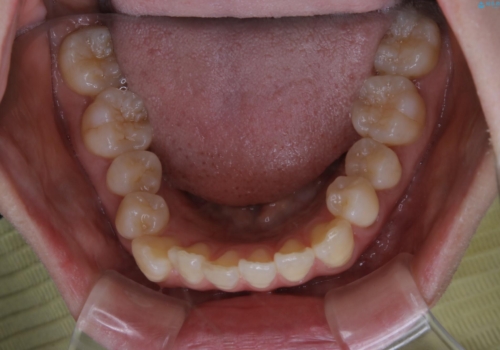

- 前歯のがたつきが気になるとご相談にいらした方です。右側前歯部のクロスバイトの他、左側にもシザーズバイトが認められたため、インビザラインにて治療を行いました。出産直後のため、ご自身の時間がなかなか取れないとの事で、最小限の来院回数で治療を勧められるように計画しました。

患者様ご自身で使用時間をしっかり管理して頂くことを条件に、最低限の来院回数で治療を進めていきました。20時間以上の使用を厳守して頂けたことで、少ない来院回数にて治療を終了することが出来ました。前よりも噛みやすくなったと大変喜んでいただけました。